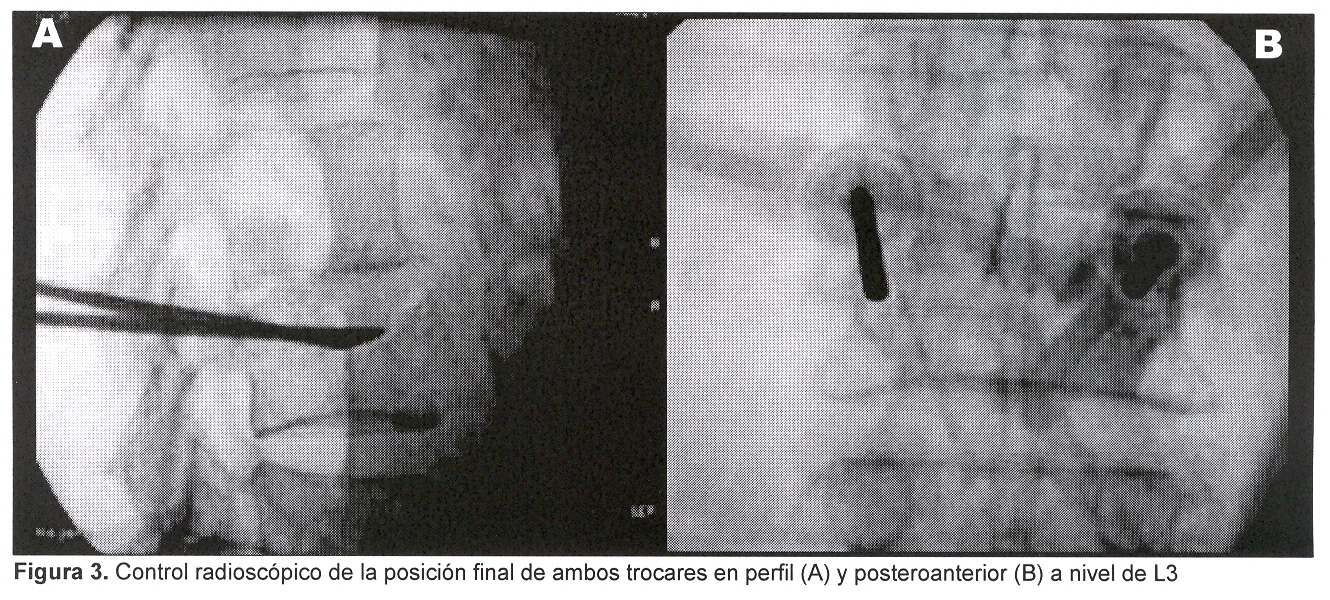

Es estudiada mediante radiografía y TC de columna vertebral lumbosacra que muestran: desmineralización difusa y disminución de la altura del cuerpo vertebral de L3, con colapso del platillo superior y pérdida de continuidad de la cortical ósea del muro posterior (figuras 1, 2 y 3).

Se procedió a realizar vertebroplastia percutánea de L3 bipedicular mediante técnica ya descripta utilizando tungsteno como contraste (figura 4).